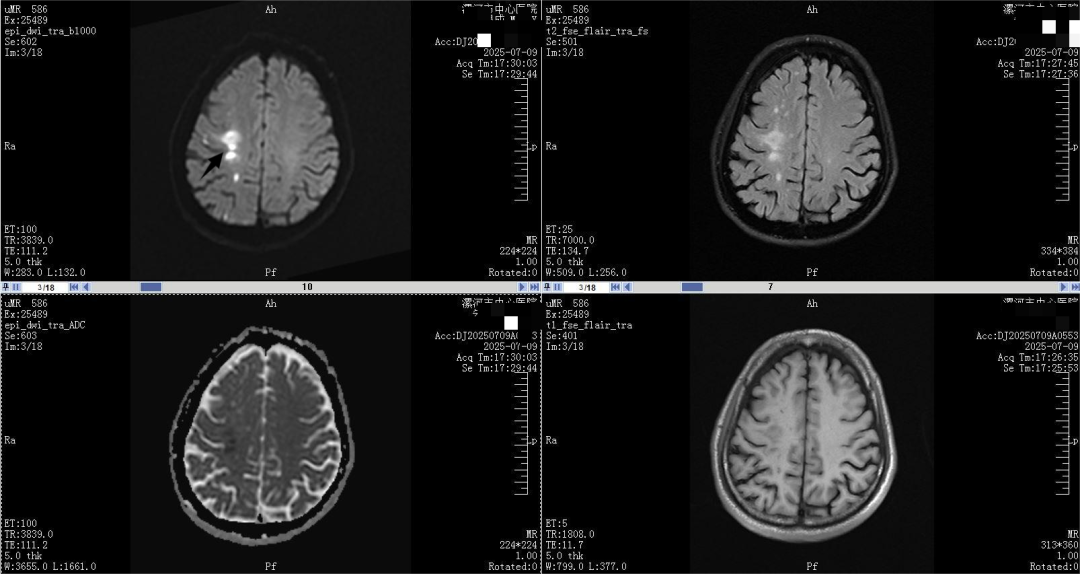

脑梗死头核磁病例